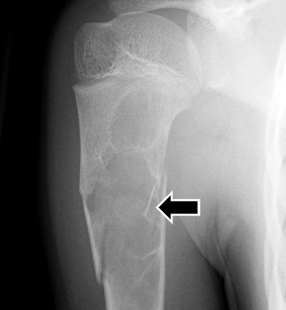

Si on parle du signe du fragment flottant, tu penses à quoi?

Kyste essentiel osseux

4

1

Not at all

2